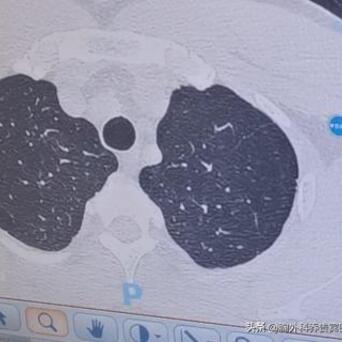

长这样的肺结节,很容易被误诊成肺癌!要是手术切了就太亏了。这位患者在1年前,就体检查出了一个肺混合磨玻璃结节,先是上网查,说是“肺混合磨玻璃结节大多数是肺癌”,再加上看了当地的医生手机配资,也说考虑是癌症。

但我看了他的CT片,这个肺结节长得比较散,并不是圆溜溜的,类似长条状的病灶,从多年临床经验来看,考虑炎症的可能性大,所以我就建议他先吃消炎药后,3个月再复查。

后来看了他复查的片子,病灶已经变淡了,别的地方还残留一些小小陈旧炎症结节,可能一辈子都不会消失,但只要定期复查就可以了。

有些肺结节因为长在胸膜附近,所以就会有胸膜牵拉,但也考虑是炎症。叮嘱患者,平时要多做些有氧运动,游泳、跑步等等,来改善肺部功能。[谢谢][玫瑰]